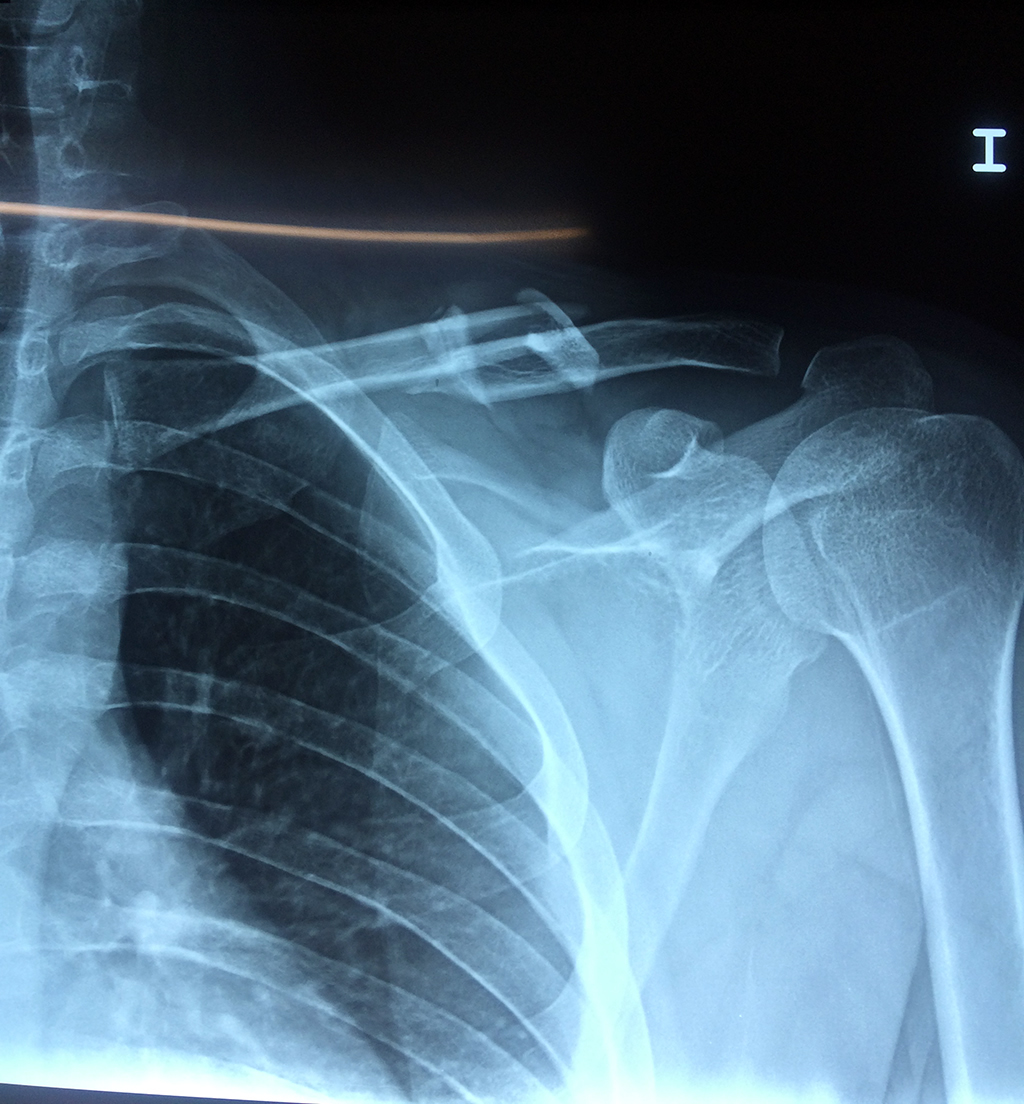

Cirugías de Calcaneo - Clavícula

La clavícula es un hueso largo, con forma de "S" itálica, situado en la parte anterosuperior del tórax. Junto con la escápula forman la cintura escapular. Se puede palpar por toda su longitud y se extiende del esternón al acromion de la escápula, siguiendo una dirección oblicua lateral y posterior.